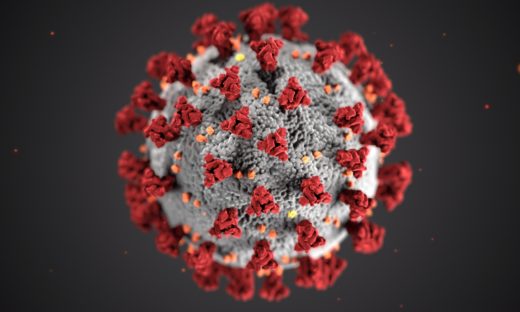

⭐️動物実験が示す不都合な真実

世界のさまざまな研究室が、違う種類の動物を使って実験を行ってきました。その結果は「違う言葉で同じ物語を語る」かのように、一貫して似た傾向を示しています。

2017年の研究⁹で分かったことは、子どもの発達期にアセトアミノフェン(熱さましの薬)を使うタイミングによって、その後の行動や脳への影響が大きく変わる「重要な時期」があるということです。

具体的には、動物の赤ちゃんが生まれて3~10日目に薬を与えると、長い間続く行動の変化が起こりました。ですが、19日目に薬を与えても、めだった影響はありませんでした。これは「種まきは一番良い季節にやらないと育たない」というのと同じで、薬の悪影響にも「特別なタイミング」があることを示しています。

また、近年の研究¹⁰ ¹¹では、いろいろな動物実験で「オス」のほうが薬の影響を強く受けやすいことが分かりました。これは自閉症が男の子に多く現れるという実際の現象とぴったり合っています。同じ鍵が異なる扉を開けるように、動物での結果が人でも起こる可能性を示しているのです。

さらに、2010年の細胞レベルの研究¹²では、アセトアミノフェンがラットの脳細胞に「アポトーシス(細胞が自分から死ぬ現象)」を起こすことが明らかになりました。そして2022年の研究¹³では、脳の細胞同士のつながり(神経突起)や細胞の骨組み(細胞骨格)に異常が出ることが分かりました。

これは、精密な電子回路の配線が傷つくことで、うまく情報が伝わらなくなるのと似ています。

さらに、2024年の研究¹⁴では、お母さんのお腹にいる時にアセトアミノフェンの影響を受けると、脳が音をちゃんと処理する力(聴性脳幹反応)がうまく働かなくなる場合があることが分かりました。これは、自閉症の子どもに見られる音への敏感さや感覚の問題と関係しているかもしれません。

こうした動物実験の発見から、薬を使うタイミング・性別などによって脳の発達への影響に差が出ることが分かってきました。これは、人間にとってもとても重要なヒントです。複数の動物実験の結果から、アセトアミノフェンが発達期に与える影響は時期や性別によって大きく変わることが分かっています。

このように、動物実験の積み重ねが、人間の脳や行動への薬の影響を知る大きなヒントになっています。